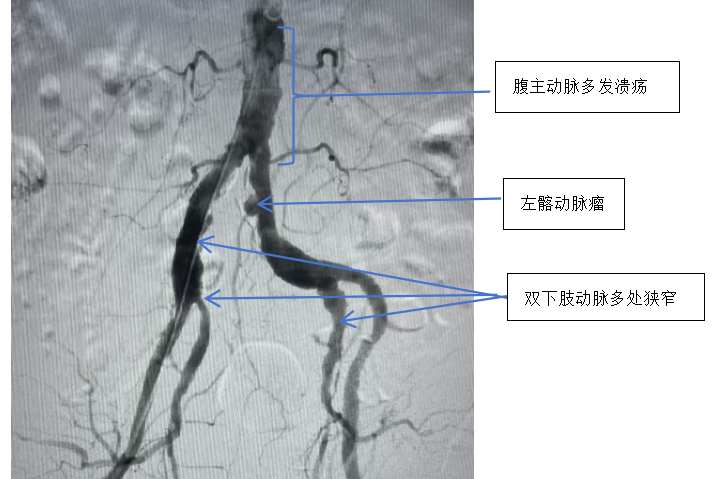

入院时患者血压高达200/100mmHg,胸腹部增强CT提示胸、腹主动脉多发壁间血肿,同时患者合并左侧髂总动脉瘤,内脏动脉和双下肢动脉斑块形成伴不同程度管腔的狭窄。

术中发现,患者左髂动脉瘤、腹主动脉多发溃疡、双下肢动脉狭窄在手术时带来了很大的挑战。放射介入科团队在张余副主任的带领下,小心通过导丝、输送支架,避免了手术对其他血管的损伤。